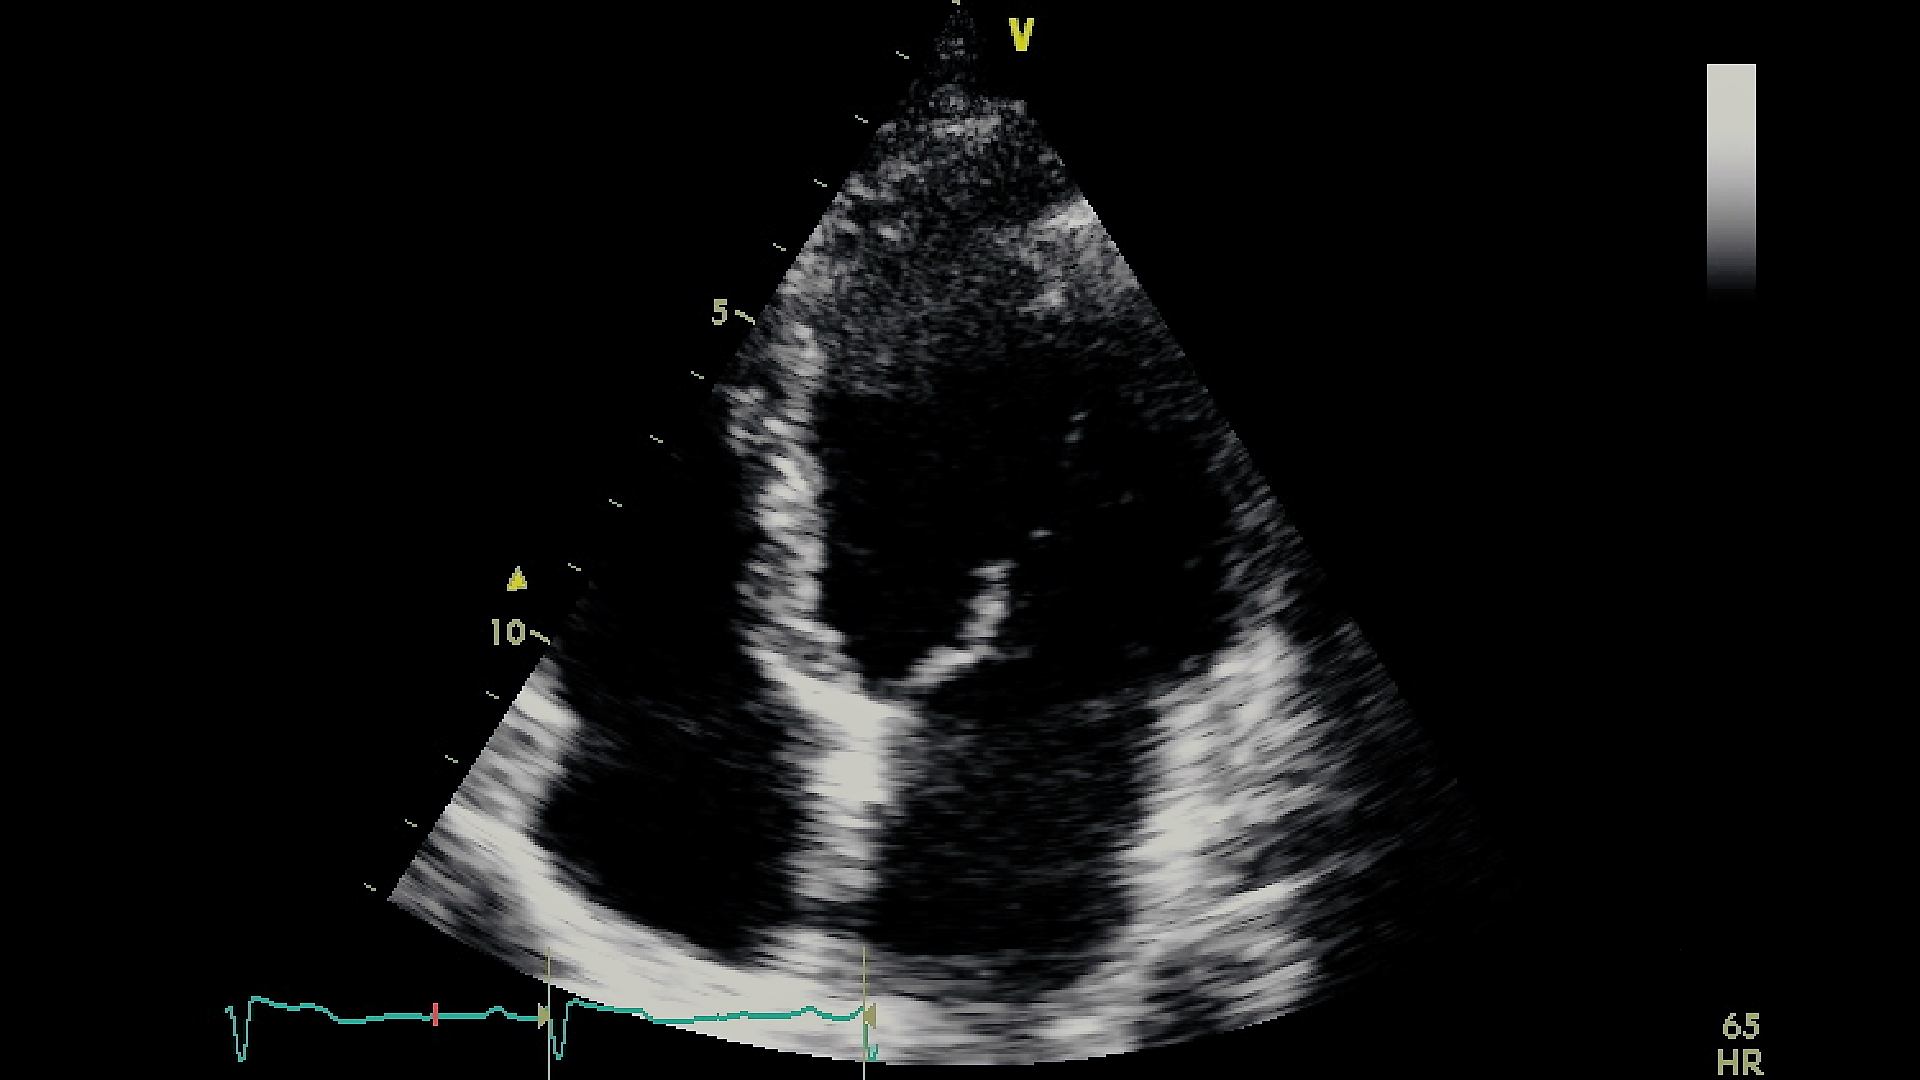

Figure 3 represents captured frames representing the quality of several videos from our dataset, which varies from good to noisy. Figures from 3(a) to 3(f) correspond to distinct frames each captured from different videos. We notice that in Figure 3(a) the left wall of the LV is blurred. Also, in Figure 3(b), the left wall of the LV is blurred and almost missing. In the same way, we observe that the totality of the LV wall is blurred in Figure 3(c); and that the interior of the LV is disrupted with noise in Figure 3(d). Finally, both Figure 3(e) and Figure 3(f) show acceptable LV representations, where the LV walls are captured and the chamber’s interior is empty from noise. Moreover, since our study is centered on the LV chamber only, we purposely ignore the distortions of the rest of the cardiac chambers (Right Ventricle, Left Atrium, and Right Atrium) in the dataset videos. For example, in Figure 3(e), both the Left Atrium and the Right Atrium are partially cut from the view, however, this does not impact our study.

Refer to caption

(a)

(b)

(c)

(d)

(e)

(f)

Figure 3: Captured frames from 6 different videos of our dataset, where each image from 3(a) to 3(f) corresponds to a distinct video. 3(a) represents a blurred left wall in the LV, 3(b) represents a missing left wall in the LV, 3(c) represents blurred LV walls, 3(d) represents noise inside the LV, and 3(e) and 3(f) represent normal echocardiograms

Hence, our final set of videos for segmentation consists of both clear and blurred video images of the LV chamber.